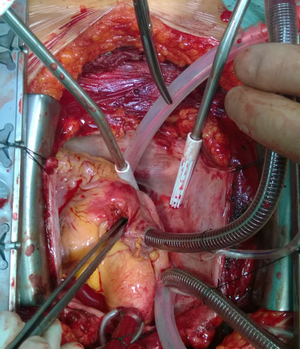

A complex self-inflicted gunshot cardiac injury in a schizophrenic patient who discontinued antipsychotic medications. The patient sustained a right ventricle and right atrium free wall gun shot injury. She presented with a moderate hemopericardium (bleeding into the pericardial sac surrounding the heart) and huge right hemothorax (shown on the CT scan). She underwent emergent surgery and bicaval cannulation for extracorporeal circulation (i.e. cardiopulmonary bypass) was performed in order to stop the heart and surgically treat the injury. Luckily, post-operation was uneventful and she returned back to her medications, fully compliant.